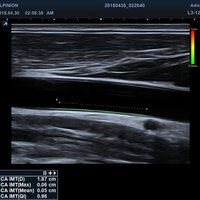

• M-Modus, Auto IMT, CV Measurement and Report, EKG, Cube Strain, Stressecho, Tissue Doppler Imaging (Kardiologie)